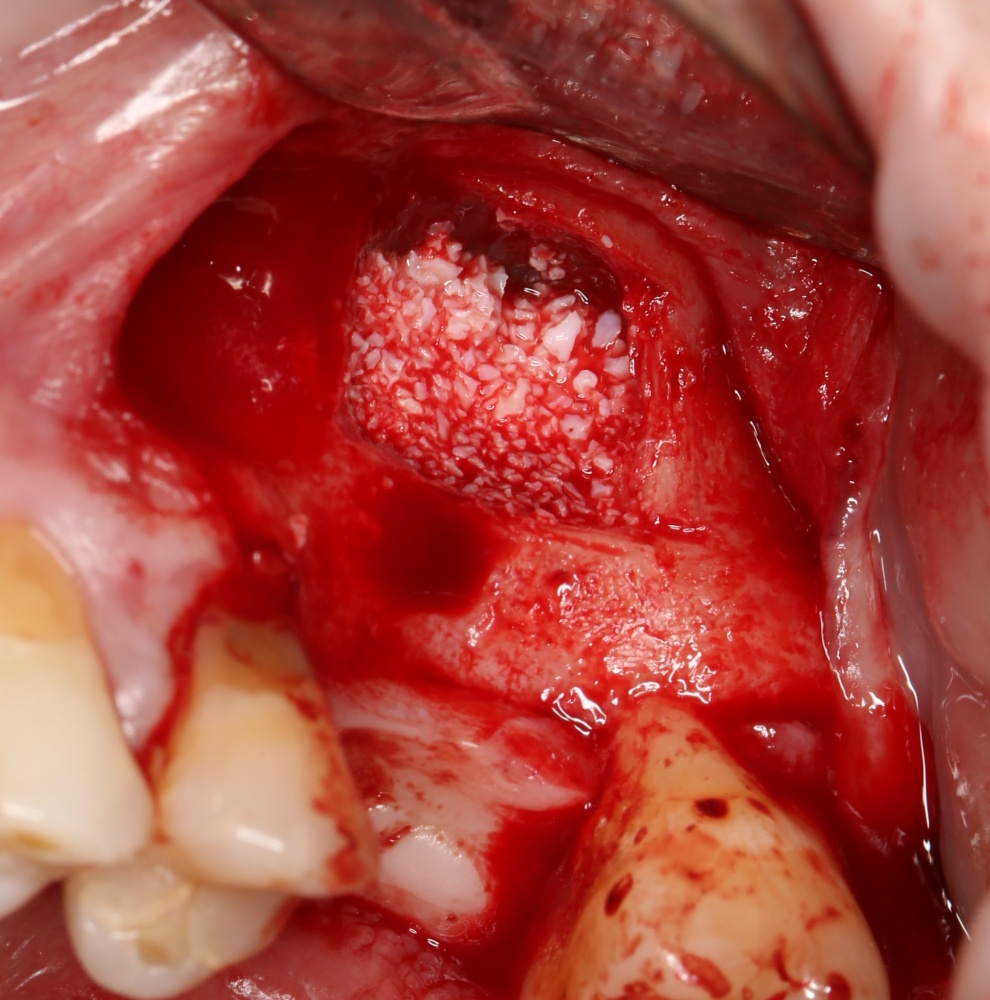

Для получения костного блока, мы открываем донорскую зону, наружную косую линию нижней челюсти.

Получение костного аутотрансплантата.

Здесь потребуется пародонтологический зонд с миллиметровой разметкой или какой-то другой измерительный прибор (операционная линейка). Ранее по КЛКТ я измерил костный дефект, теперь нужно нанести границы будущего костного блока на донорскую зону.

Для получения костного блока мы использовали ультразвуковую пьезохирургическую систему. Это самый удобный и безопасный инструмент для проведения подобных манипуляций. С помощью него мы сформировали и выделили костный блок. Он должен отделяться легким движением остеотома или элеватора. Как это сделать правильно — читай здесь>>

Возвращаемся к основной операционной области. Еще раз посмотрим на альвеолярный гребень, поофигеваем от его ширины и моих грандиозных планов:

Я зафиксировал костный блок практически без адаптации на несколько винтов. Обрати внимание, что винты находятся в зоне, где не планируется установка имплантатов. Фиксация должна быть надежной, поскольку мне еще предстояла подготовка лунок для имплантатов. Трех винтов для этого вполне достаточно.

Дальнейшая адаптация костного блока свелась к сглаживанию острых краев. После чего я приступил к подготовке лунок и установке имплантатов.